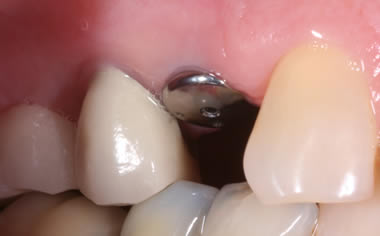

More back teeth replaced by dental implants

Case Five (4 images)